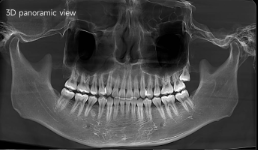

CBCT pada Penatalaksanaan Cleft Lip and Palate (Bibir Sumbing)

Radiografi lateral cephalometric adalah salah satu metode utama dalam ortodonti untuk menilai hubungan antar struktur rahang dan wajah. Dengan analisis sudut-fasial seperti model Downs, dokter

Fibrous dysplasia adalah kelainan jaringan tulang jinak di mana jaringan fibrosa menggantikan jaringan tulang normal, mengakibatkan deformitas, penebalan tulang, dan perubahan fungsi. Di daerah maksilofasial,